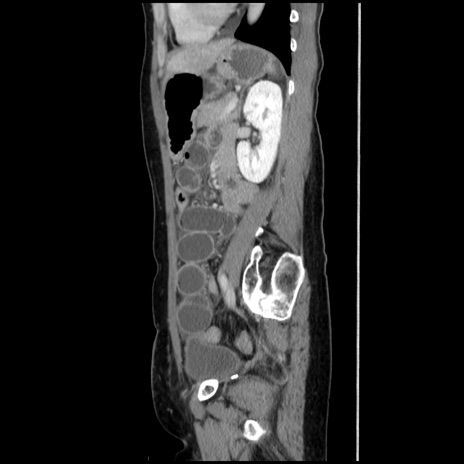

症例32(矢状断像)

冠状断像